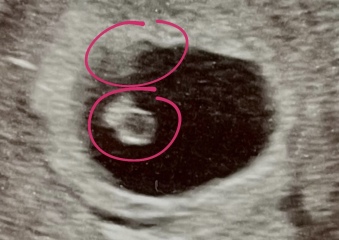

Donimo · 14/06/2024 18:14

I'm no expert at looking at scans but my first scan at almost 7 weeks was very clearly twins and the person doing the scan immediately said I can see 2 heartbeats. They were identical.

This is is my scan which is quite clear as 2.